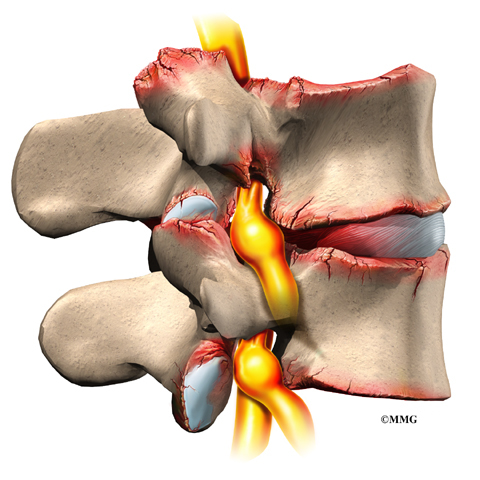

Остеоартрит фасеточных суставов: медицинские снимки и схемы